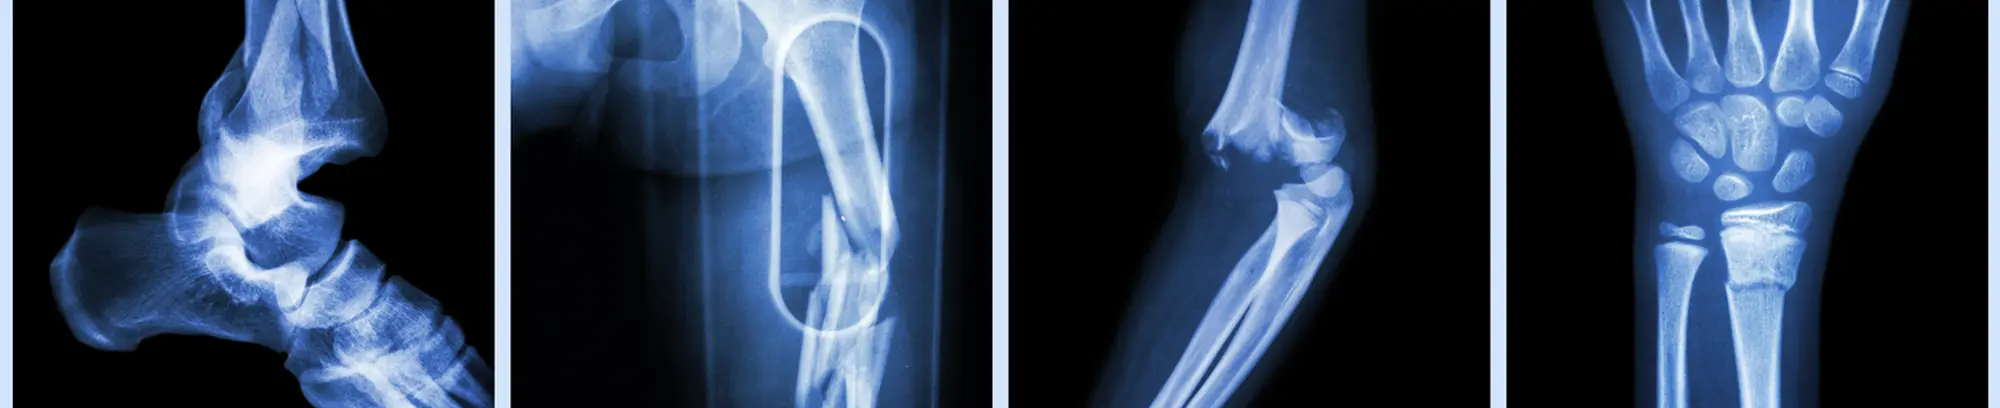

Trauma Surgery and Fracture Management

Trauma surgery is a subspecialty of orthopedic medicine that requires fellowship training beyond the usual orthopedic surgical residency. Our orthopedic trauma and reconstruction surgeons treat and manage the simplest to the most complex fractures. Dr. Austin Hill, Dr. David Laverty, Dr. Mark Parrella, Dr. Claire Ryan, Dr. Vilas Saldanha, Dr. Blake Schultz, Dr. Ryan Taylor, and Dr. Blake Turvey are also highly involved in the advancement of orthopedic trauma surgery techniques. Dr. Laverty has over a decade of experience caring for injured patients at the region’s only Level 1 trauma center, University Medical Center Brackenridge.

Common orthopedic trauma injuries and treatment options include: